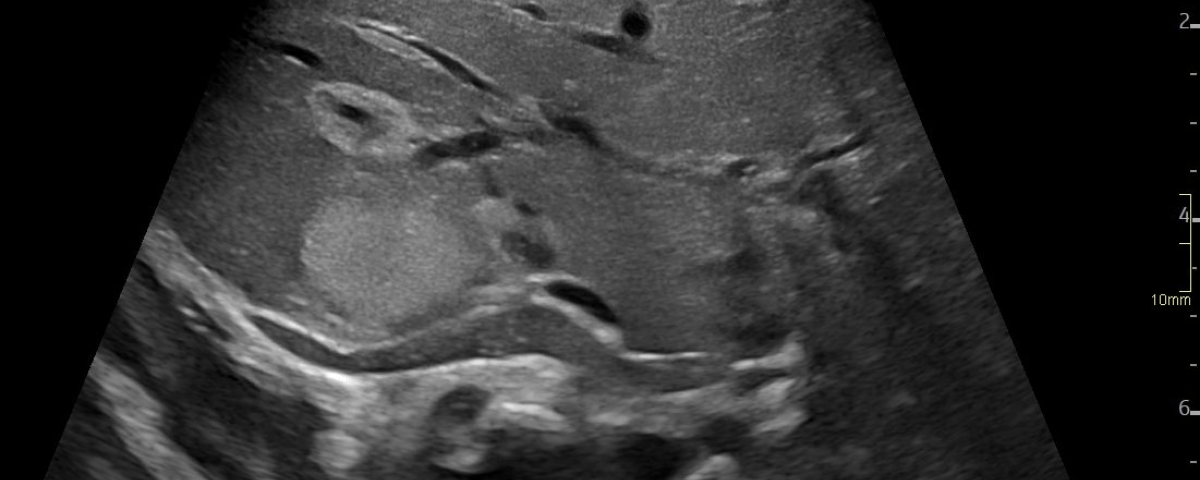

A: B-Mode image in the axial plane demonstrating multiple hyperechoic, well-defined lesions in the liver. Other lesions demonstrate a hypoechoic central area.

Multiple hepatic lesions were identified on ultrasound (A). Some lesions appeared as typical, well-defined hyperechoic cavernous hemangiomas (2), while others demonstrated large, tortuous vessels. Additional lesions showed a hyperechoic rim with a hypoechoic center and internal Doppler flow, consistent with capillary hemangiomas (2). In some HH (B), arteriovenous shunting was suspected. However, Triplex Doppler examination demonstrated normal hepatoportal flow in the portal vein (C) with flow velocities below 40 cm/s – within the normal range for the age – as well as a normal triphasic flow pattern in the hepatic veins (D).